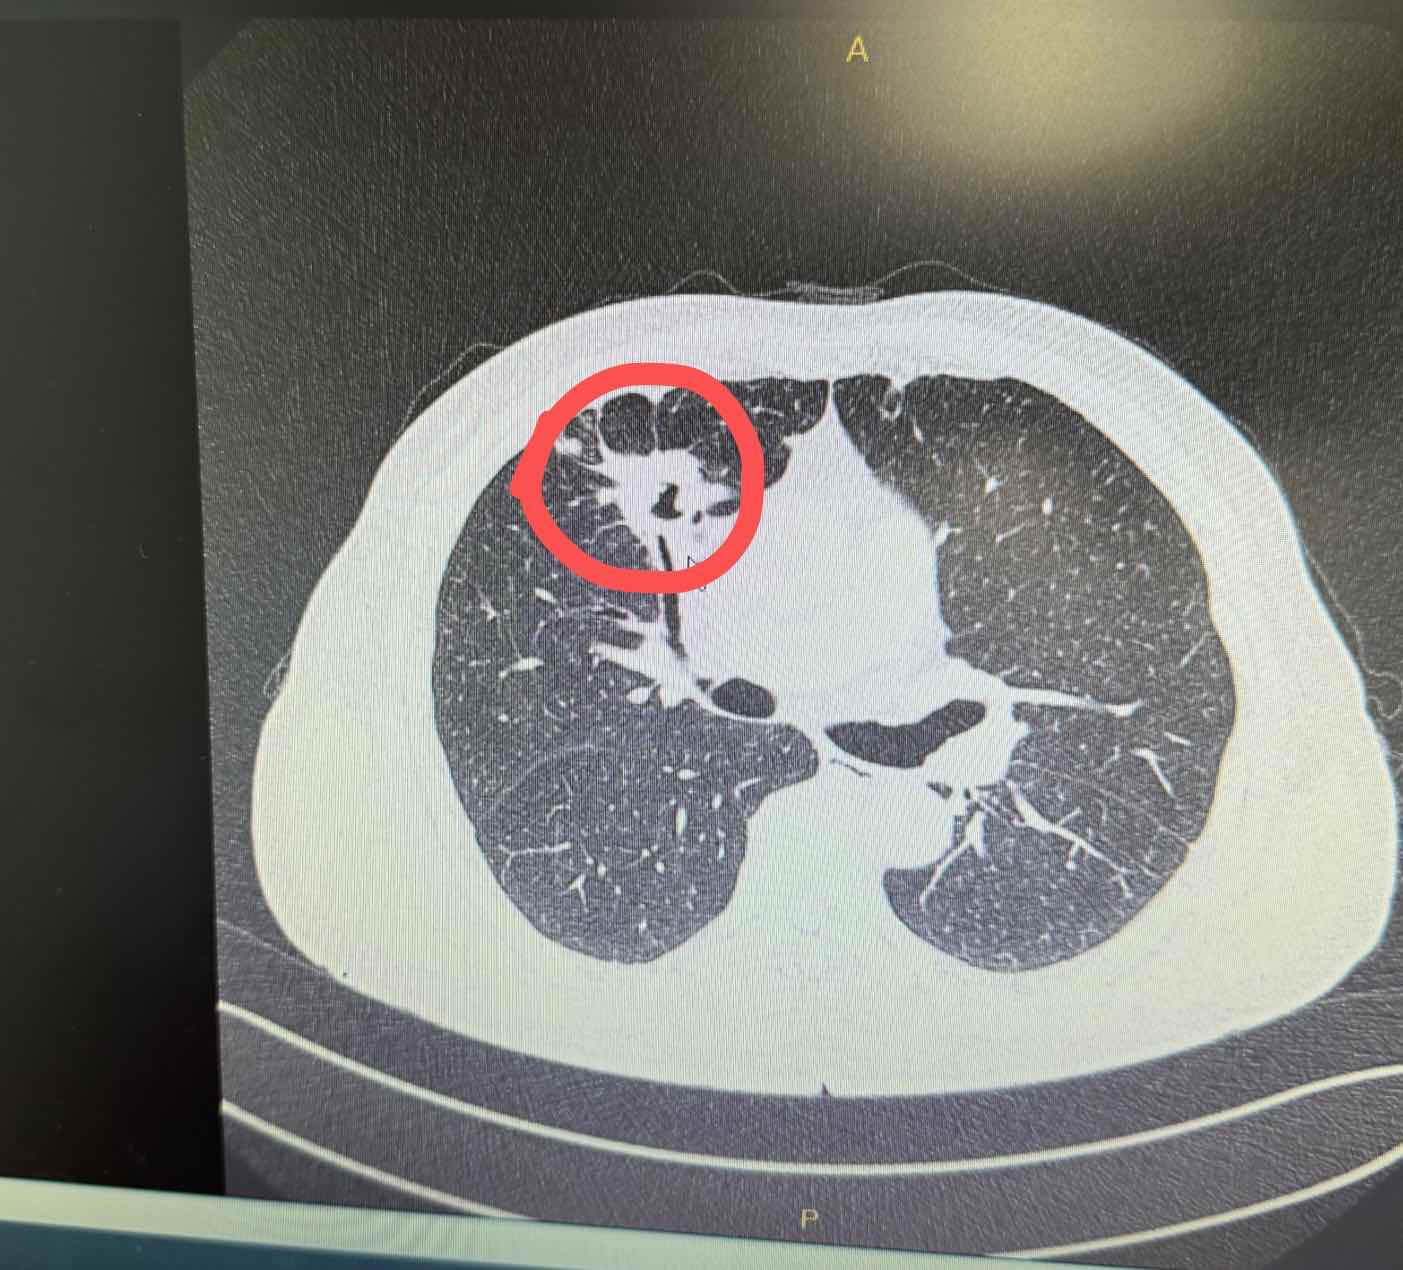

病人19缺失,拷贝增加 13%,无其他基因突变。从化疗到阿法替尼,近四年,近日因头部及主灶边上有异常,不得不换药试试。由于奥希非一线不让报,只能白盒先来解决了,希望一切向好,突然有个想法,老人脑MRI有微小密度影从入脑角度是不是换达可替尼也行,毕竟主病灶这半年从缩小到稳定,但有一点不明白,主灶边上的到底什么情况?三个月复查有增大。感谢大家指点